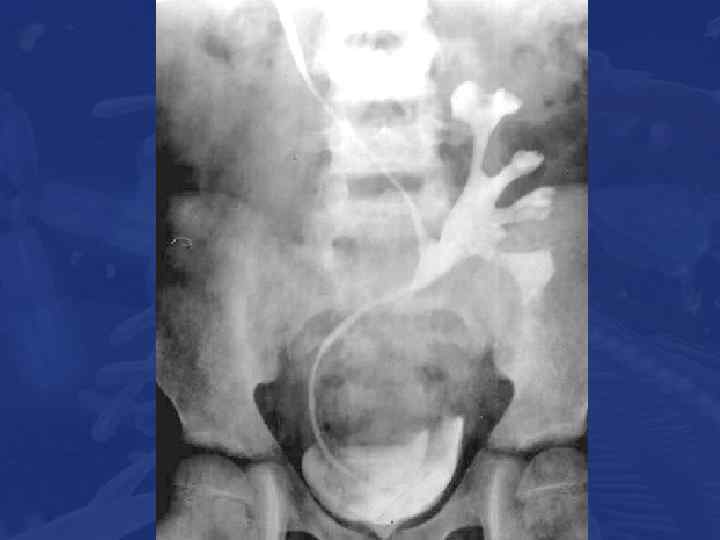

Претрансплантационная подготовка • Определение сенсибилизации • • Оценка мочевого тракта Выявление скрытых инфекций Nephroureterectomy Коррекция функции мочевого пузыря

Surgical aspects of kidney transplantation Vascular anastomosis 59

ВЫХОД Хирургические аспекты трансплантации почки детям. Сосудистые анастомозы. 60 14